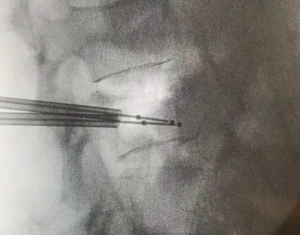

Vertebroplasty is a minimally invasive operation with a pinhole, injecting artificial bone powder (acrylic adhesive) into the vertebral body. Vertebroplasty was completed with fractures of the 12th thoracic spine and the 3rd lumbar spine